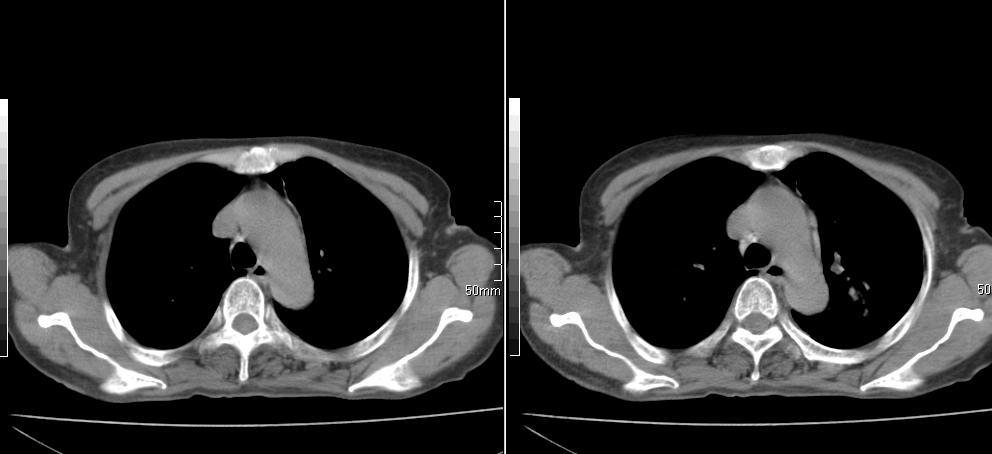

标题: CT26857:女,60岁,胃部不适前来就诊,不咳嗽,乏力,胸椎 [打印本页]

标题: CT26857:女,60岁,胃部不适前来就诊,不咳嗽,乏力,胸椎

1、胸椎有骨质破坏伴周软组织,考虑胸椎转移。2、考虑左肺上叶尖后段支气管开口区周围型肺癌可能。

1、胸椎有骨质破坏伴周软组织,考虑胸椎转移。2、考虑左肺中央型肺癌可能。

椎体有高密度影,多系转移。

支持中央型肺癌,胸椎转移。

左肺中央型肺癌,胸椎大致正常,必要时ect扫描